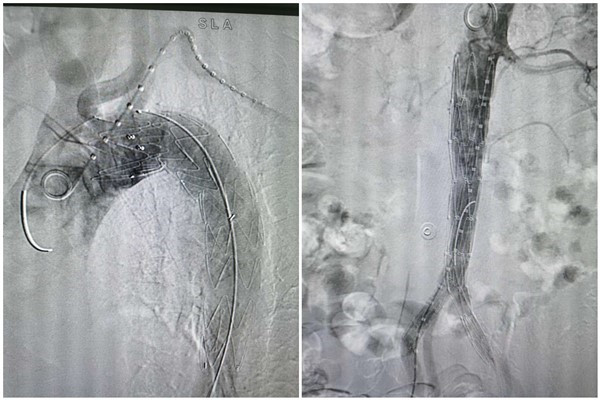

患者查女士,因呼吸困难、胸闷至我院,郑强荪院长接诊后综合分析了患者的病情及检查结果,为其行主动脉CTA检查,检查提示主动脉弓、降主动脉至双肾动脉水平管腔内见片状低密度分隔,将管腔分为左右两腔,考虑主动脉夹层Stanford B型。郑强荪院长综合分析病情后决定为其行主动脉夹层腔内隔绝术。患者周先生,于我院康复医学科住院期间突发胸痛,左侧胸部、胸骨后压榨性疼痛,伴大汗淋漓,难以忍受,持续不缓解,心内科急会诊后建议行主动脉CTA。结果提示主动脉弓、胸、腹主动脉及其分支动脉粥样硬化样改变并多发溃疡形成,主动脉下段(约腰3椎体水平)穿通性溃疡形成,主动脉下段(约平腰3椎体水平)至左侧髂总动脉、髂外动脉上段壁内血肿,肠系膜上动脉起始部混合斑块并管腔中度狭窄。邓捷主任医师会诊后考虑患者病情危重,需要尽快行主动脉夹层腔内隔绝术。

这两位患者的手术由邓捷主任医师及其带领的心内科介入团队进行。在手术当中,邓捷主任医师为患者精心测量主动脉锚定区的长度、锚定区到破口的长度、主动脉各段的直径,选择好适合的覆膜支架,并设计好最优化的手术方案,成功完成一例主动脉夹层Stanford B型腔内隔绝术及一例腹主动脉夹层腔内隔绝加髂动脉分叉重建术。绑在患者身上的定时炸弹成功被拆除,患者顺利安返病房。